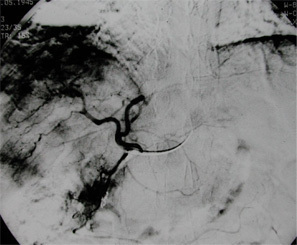

通过影像学定位诊断可以更进一步的做出诊断,影像学手段包括b超,ct,同位素干扫描,肝血管照影,核磁共振等发现肝脏有占位性病变时,均应考虑患有肝癌的可能性,应做更进一步的检查,进一步的检查一般为检查血清中的甲胎蛋白含量,如果血清中甲胎蛋白呈阳性,且含量大于200 200μg、持续8周以上者或甲胎蛋白含量大于400μg持续4周者,均应考虑患有肝癌,如影像学检查已发现肝脏有占位性病变的话即可明确诊断为肝癌。